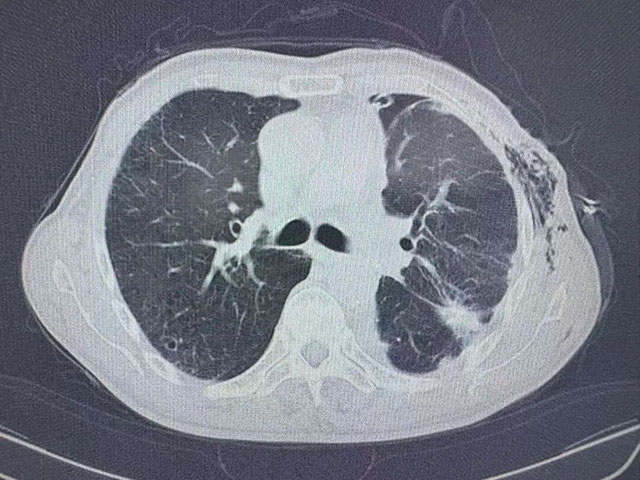

术前胸部CT

入院时,张爷爷的病情已十分危急,胸心外科副主任刘浩副教授检查发现:左肺存在恶性结节,左侧胸腔中量积液,肺部感染严重。